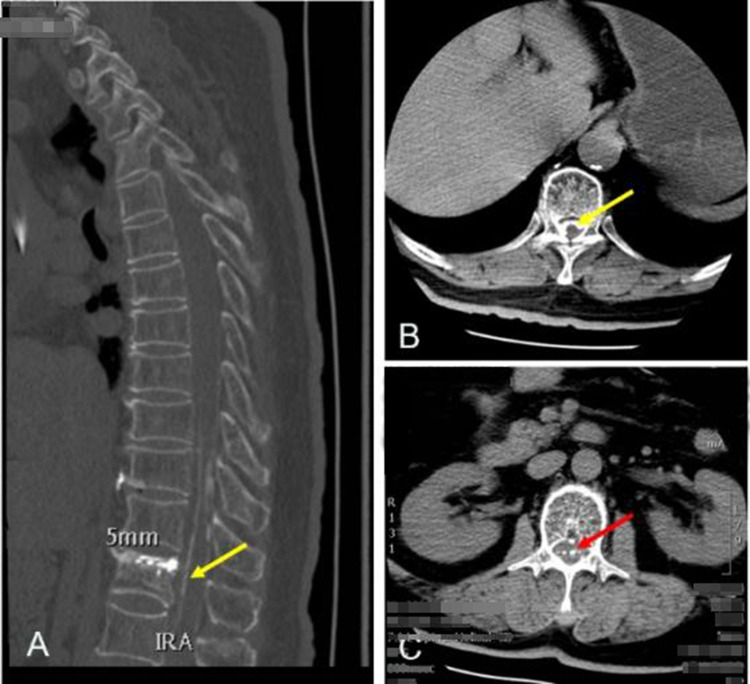

Case report: We designed a prospective cohort study to evaluate the outcomes following of percutaneous vertebroplasty using GeneX in patients with osteoporotic vertebral compression fractures. Vertebroplasty was performed at seven vertebrae in the first seven patients. Overall, there were four leaks in four (57%) of the seven patients. Asymptomatic leak of the GeneX material into the intradiscal and paravertebral structures at the treated vertebral level was observed in three patients (43%). However, the material leaked into the intradural and epidural space in the seventh patient (14%), causing severe neurological deficits. Primary diagnosis was bone cement implantation syndrome. The patient's neurological status improved gradually during the month after surgery. She was able to resume her activities of daily living and had regained her urinary function by 3 months after surgery.